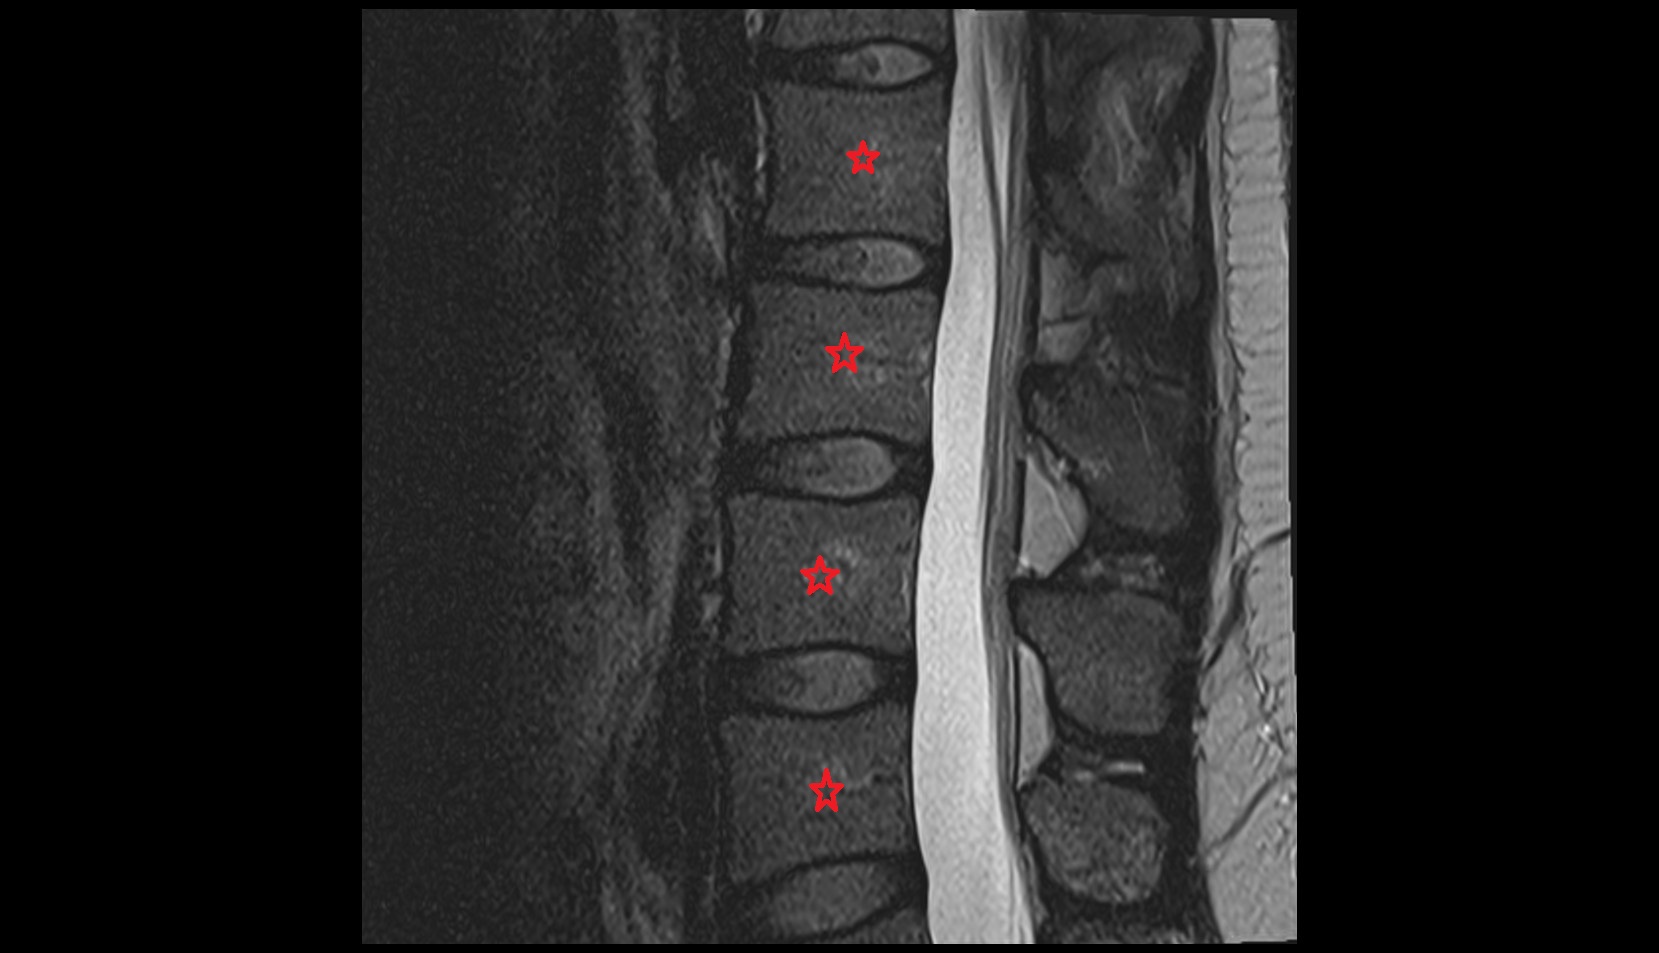

- L5–S1 Intervertebral disc

- L4–L5 Intervertebral Disc

- L3–L4 Intervertebral Disc

- L2–L3 Intervertebral Disc

- L1–L2 Intervertebral Disc